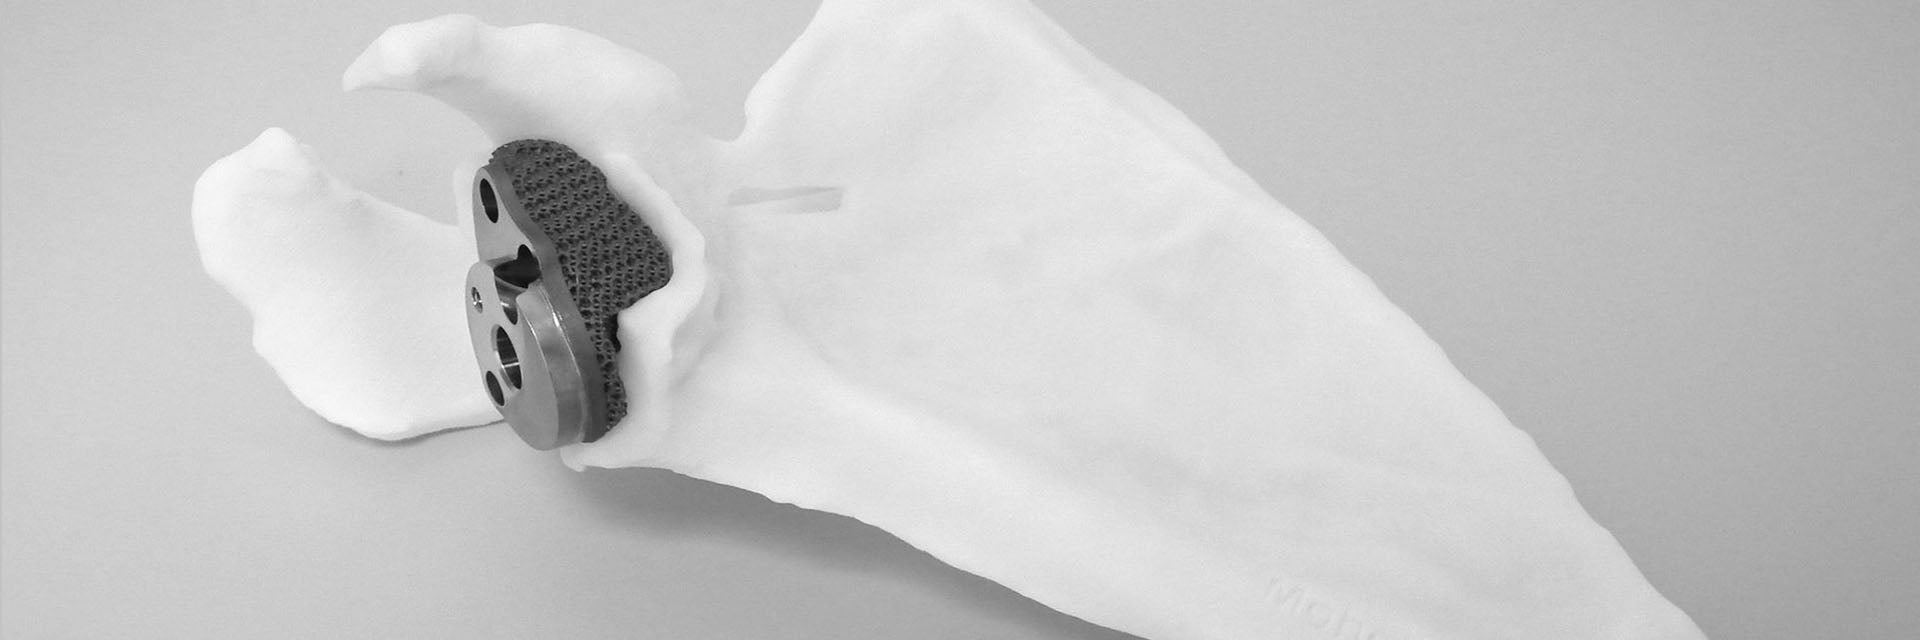

Dr. Van den Bogaert worked with Materialise’s clinical engineering team to define the best design for the custom-made glenoid implant, which included a baseplate for a reverse shoulder replacement prosthesis augmented with a porous structure exactly matching the patient’s glenoid cavity.

Preoperative planning included optimizing the baseplate's position to reconstruct the joint center of rotation to an anatomical position as much as possible. In addition, screw position and orientation were fully customized, to address the strongest parts of the (remaining) scapular bone.

The custom-made titanium implant was manufactured with 3D printing. Next, 3D-printed, personalized guides were designed to guide the accurate positioning of the implant, the pre-drilling of the screw holes, and the fixating of the screws during surgery. The custom-made instruments greatly facilitate the intervention by allowing surgeons to accurately transfer the preoperatively planned component placement and screw positioning during surgery.